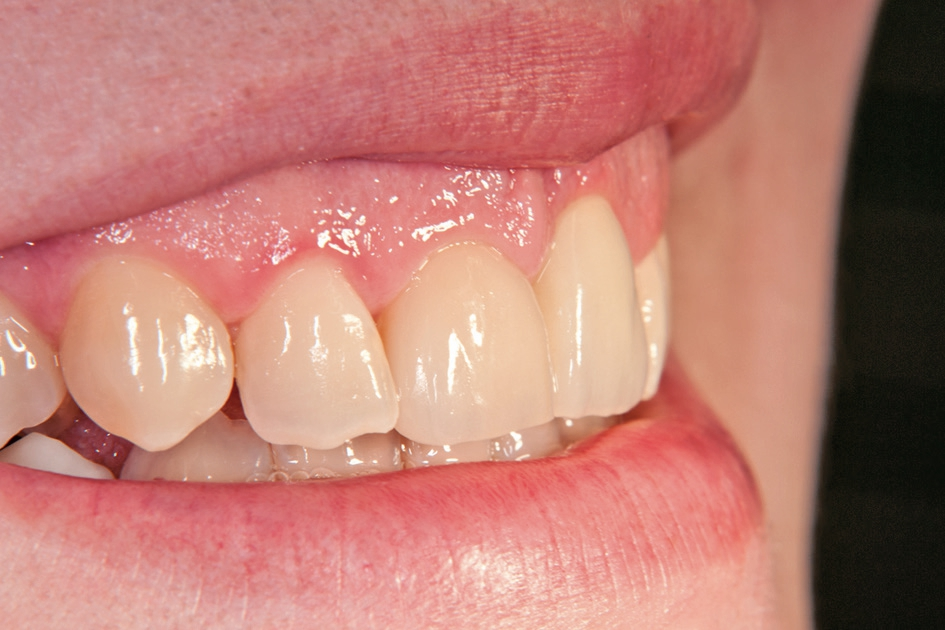

Gleichzeitig mit der prothetischen Versorgung des Implantats wurde auch für Zahn 11 ein Veneer geplant. Zum Einsatz kam ein Zeramex T Implantat Durchmesser 5,5 mm, Länge 12 mm. Für die Kronenversorgung wurde ein mit e. Max überpresstes CAD-Abutment gewählt. Während der Einheilphase des Implantats kam eine Sunflex-Prothese zum Einsatz.